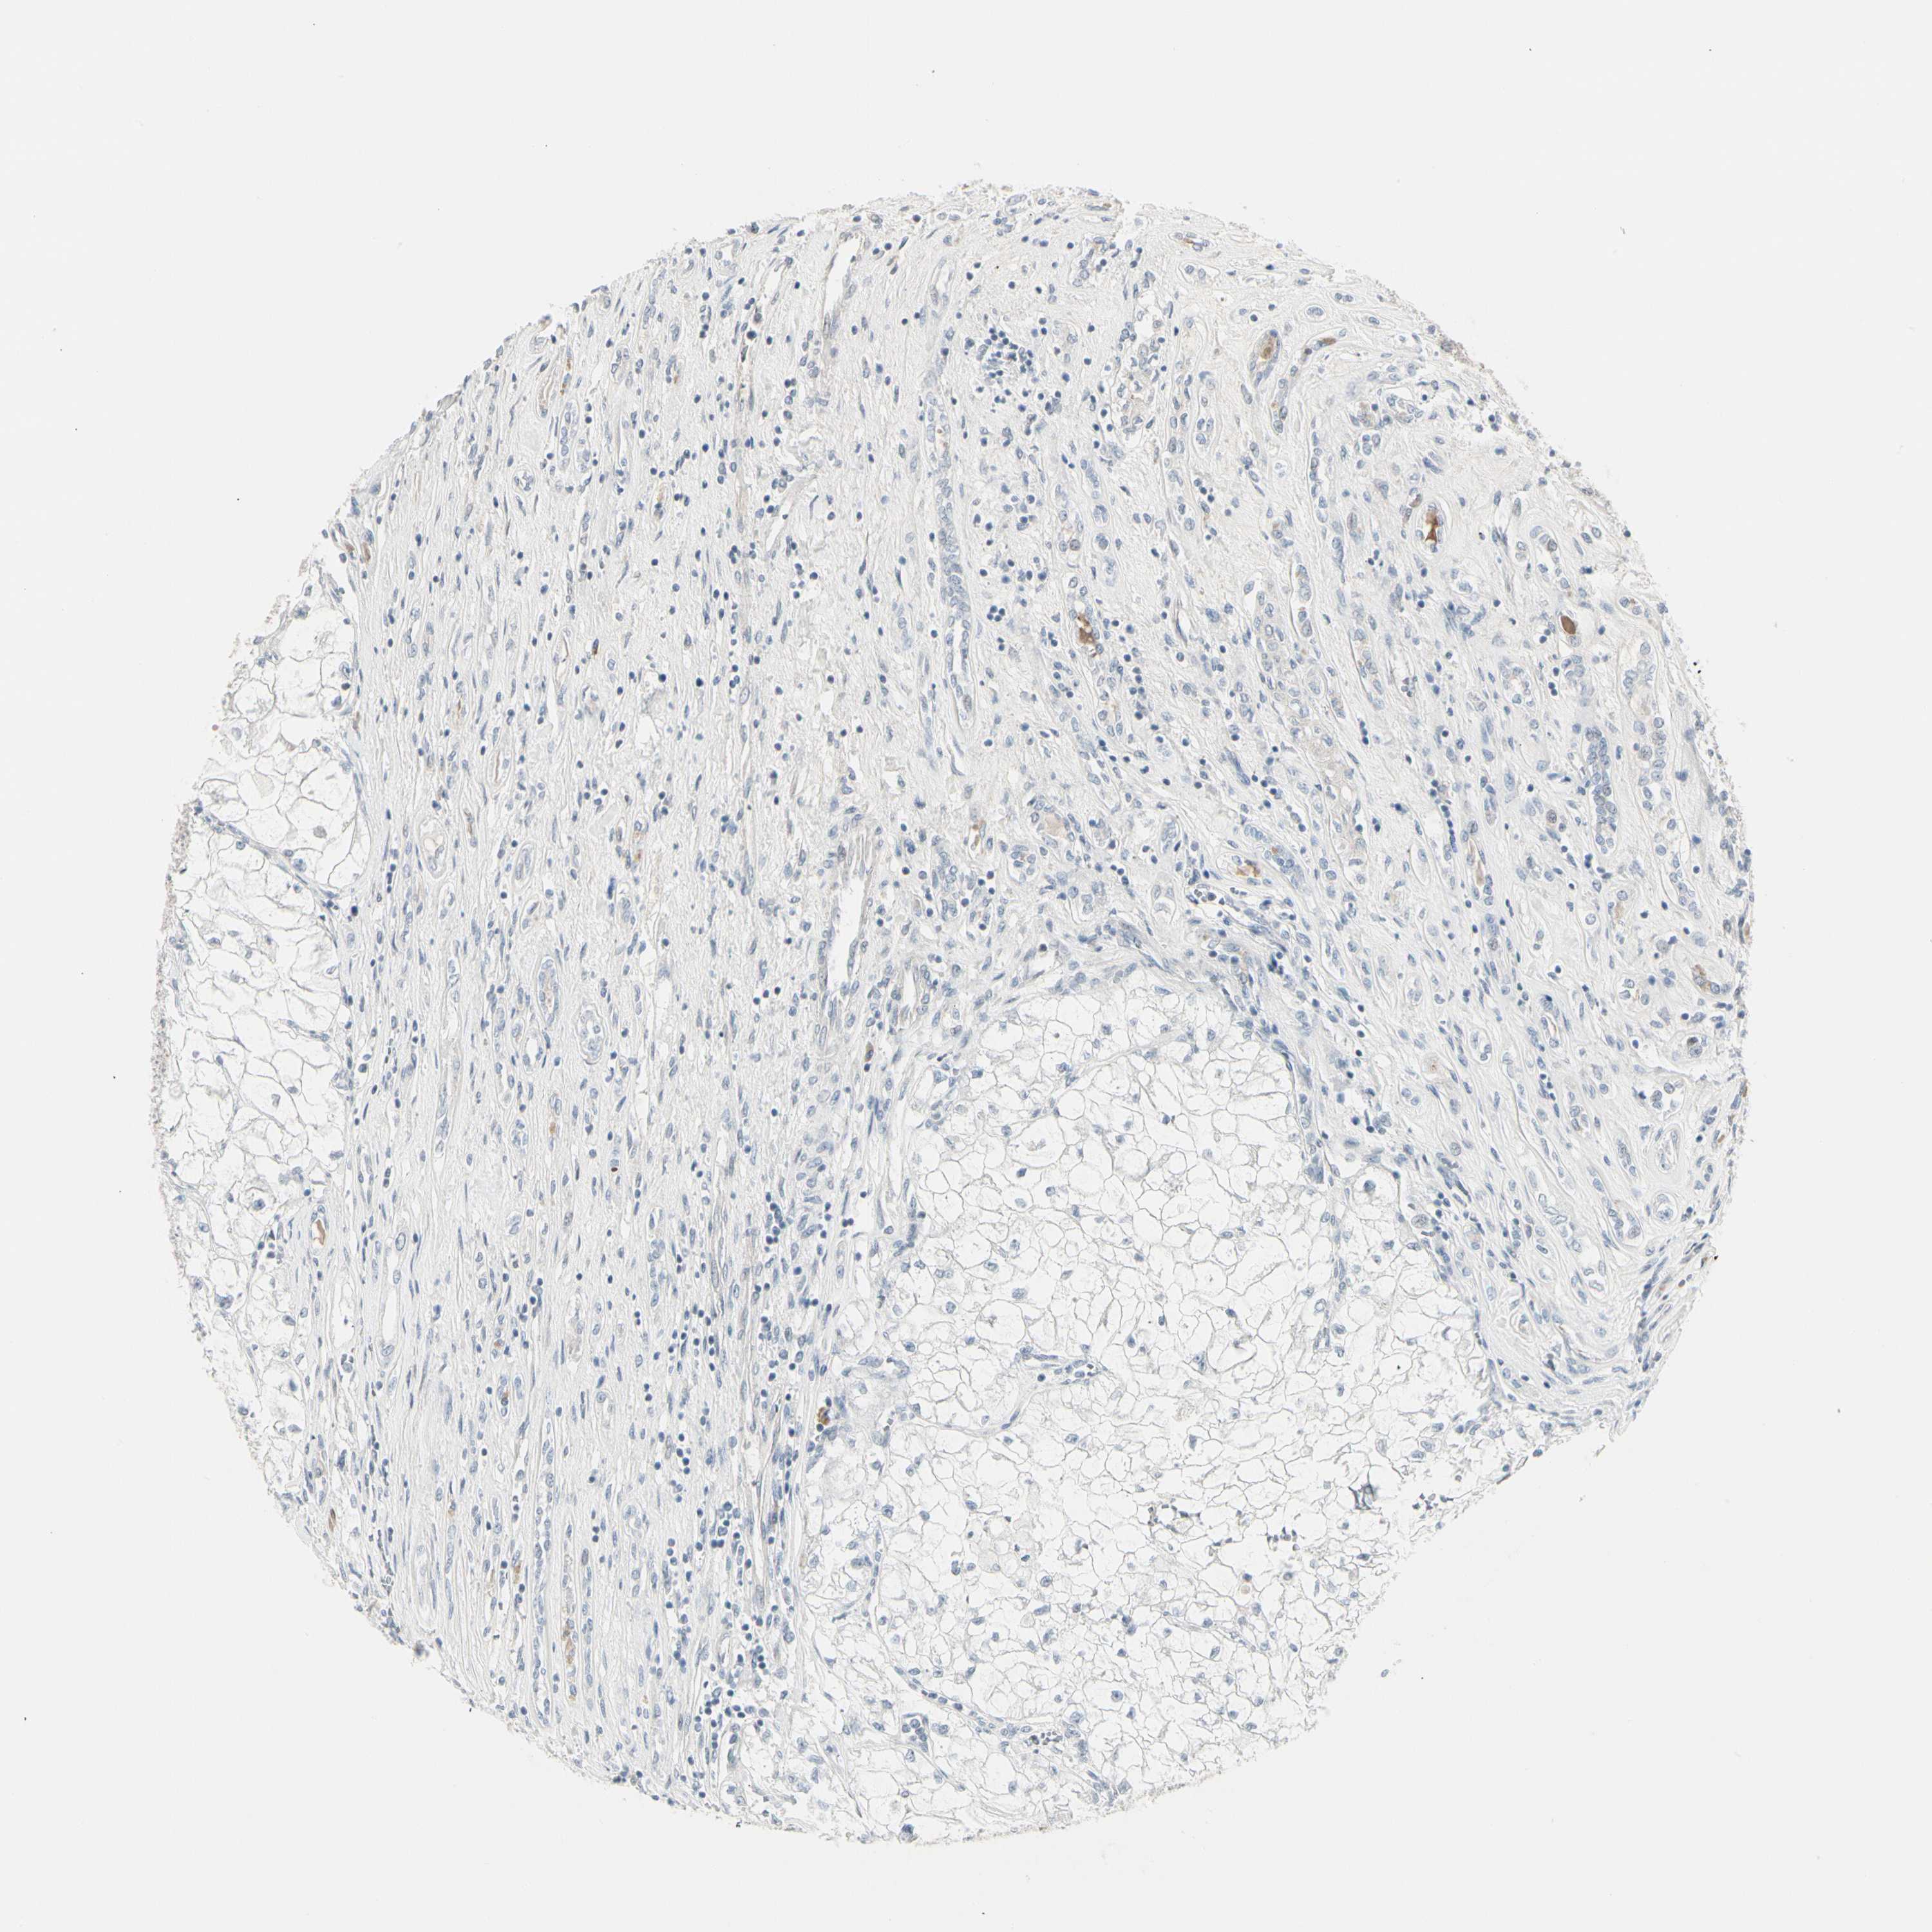

KIDNEY RENAL CLEAR CELL CARCINOMA (VALIDATION) - Interactive survival scatter ploti

The Survival Scatter plot shows the clinical status (i.e. dead or alive) for all individuals in the patient cohort, based on the same data that underlies the corresponding Kaplan-Meier plots. Patients that are alive at last time for follow-up are shown in blue and patients who have died during the study are shown in red.

The x-axis shows the expression levels (FPKM) of the investigated gene in the tumor tissue at the time of diagnosis. The y-axis shows the follow-up time after diagnosis (years). Both axes are complimented with kernel density curves demonstrating the data density over the axes. The top density plot shows the expression levels (FPKM) distribution among dead (red) and alive patients (blue). The right density plot shows the data density of the survived years of dead patients with high and low expression levels respectively, stratified using the cutoff indicated by the vertical dashed line through the Survival Scatter plot. This cutoff is automatically defined based on the FPKM cutoff that minimizes the p-score. The cutoff can be changed by dragging the vertical line or by entering a cutoff value in the square labeled "Current cut-off".

Under the Survival Scatter plot the p-score landscape (black curve; left axis) is shown together with dead median separation (red curve; right axis). Dead median separation is the difference in median mRNA expression between patients who have died with high and low expression, respectively. It is calculated as follows: median FPKM expression of dead patients with high expression - median FPKM expression of dead patients with low expression. This is intended to aid the user in visually exploring custom cutoffs and the associated p-scores and dead median separation.

Individual patient data is displayed and can be filtered by clicking on one or more of the category buttons on the top of the page. Categories describing expression level and patient information include: high, low, alive, dead, female, male and tumor stages. The scale of the x-axis can be toggled between linear and log-scale by clicking on the "x log" button. Mouse-over function shows TCGA ID, patient information and mRNA expression (FPKM) for each patient.

& Survival analysisi

Kaplan-Meier plots summarize results from analysis of correlation between mRNA expression level and patient survival. Patients were divided based on level of expression into one of the two groups "low" (under cut off) or "high" (over cut off). X-axis shows time for survival (years) and y-axis shows the probability of survival, where 1.0 corresponds to 100 percent.

DMPK is not prognostic in Kidney Renal Clear Cell Carcinoma (validation)

Best expression cut offi

Based on the FPKM value of each gene, patients were classified into two groups and association between prognosis (survival) and gene expression (FPKM) was examined. The best expression cut-off refers the FPKM value that yields maximal difference with regard to survival between the two groups at the lowest log-rank P-value. Best expression cut-off was selected based on survival analysis .

When clicking on this number, the vertical dashed line indicating cut-off, the interactive survival plot, and the Kaplan-Meier curve will be adjusted to show results based on the best expression cut-off.

: 10.02

P scorei

Log-rank P value for Kaplan-Meier plot showing results from analysis of correlation between mRNA expression level and patient survival.

N/A

TCGA RNA samplesi

RNA-seq data is reported as average FPKM (number Fragments Per Kilobase of exon per Million reads), generated by the The Cancer Genome Atlas (TCGA) .

Normal distribution across the dataset is visualized with box plots, shown as median and 25th and 75th percentiles. Points are displayed as outliers if they are above or below 1.5 times the interquartile range. FPKM values of the individual samples are presented next to the box plot.

Average pTPM 9.0

Number of samples 100